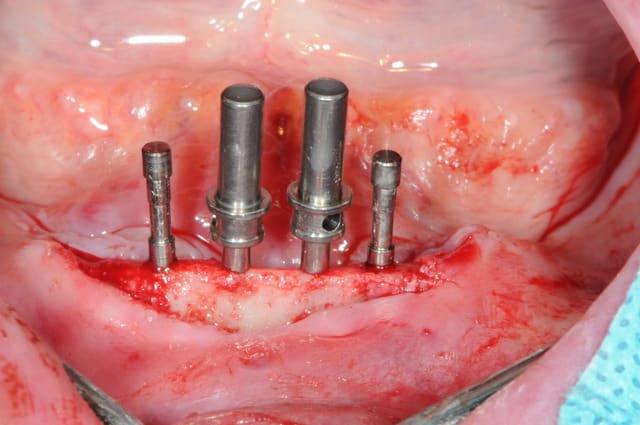

Bon, je viens de lui poser ses 4 mini-implants ce matin.(diamètre2.8 longueur 13mm)

je crois que comme ils ne sont pas trop mal disposées, je vais les solidariser par une barre d'Ackerman plutôt que 4 boules.

Pour les 4 minis implants, au moins c'est pas du 2.0 mm

Petite remarque, je trouve que les implants sont trop en ligne, pas assez de distribution antéro-postérieur. Placés sur une courbe, on a une meilleur distribution des forces.

Aussi, aurait-il été possible de les placer plus distalement ?

Pourquoi pas placer 4 implants 3,8 mm avec une légère plastie verticale ? La chirugie est 95 % la même.

plus distalement, il y avait un os en néoformation donc insatisfaisant pour une stabilité primaire des implants, mais surtout, le relief osseux était désastreux.

en fait la plastie à été faite sur 3 bon millimètres et je ne trouvais pas la position distale vraiment alléchante.